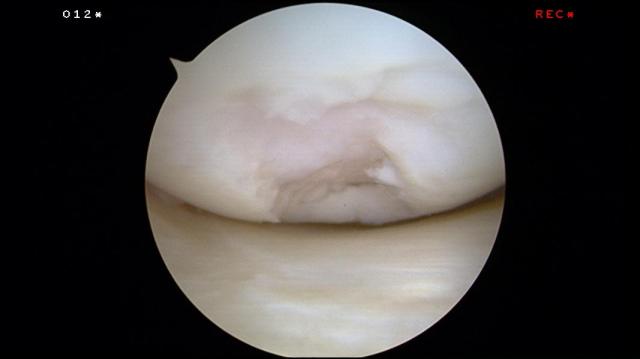

This is how it looks like during arthroscopy:

The torn cartilage was found floating inside the knee. Sometimes it cannot be found.